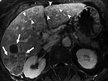

Aknu audzēji